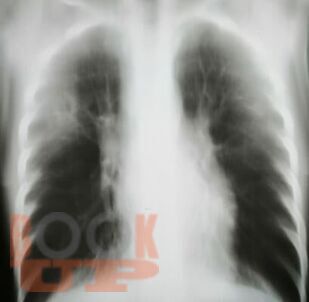

Учебное пособие составлено в соответствии с требованиями ФГОС ВО по специальностям 31.05.01 Лечебное дело и 31.05.02 Педиатрия, рабочей программы дисциплины «Фтизиатрия». В пособии представлена клиническая классификация туберкулеза, но сделан акцент на локализацию туберкулеза органов дыхания, иллюстрированная рентгенологическими снимками больных, лечившихся в КГБУЗ «Красноярском краевом противотуберкулезном

диспансере №1» с 1980-х г. по настоящее время, также даны определения различным формам туберкулеза органов дыхания.